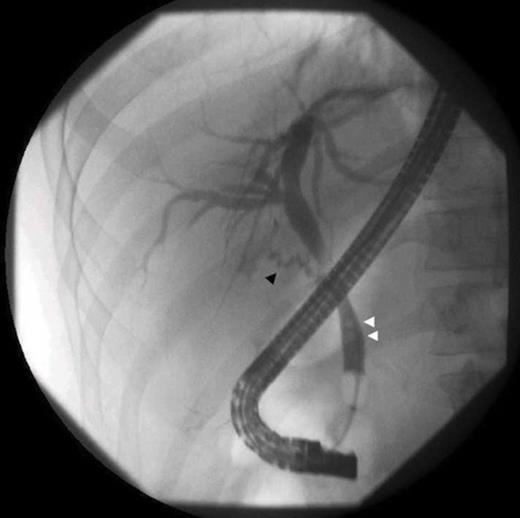

Over seven months, he had continued frequent recurrent attacks of acute cholecystitis, and choledocholithiasis. His symptoms included frequent nausea, vomiting, persistent sharp right upper quadrant pain, fever, and jaundice, which precipitated multiple Emergency Department visits to multiple institutions. The patient presented to our institution with an outside ultrasound that demonstrated multiple residual stones, a sonographic Murphy’s sign, and dilated common bile duct of 9 mm. Choledocholithiasis was confirmed by MRCP (Fig. 1) and gallstones were visualized in the remaining portion of the gallbladder by CT, (Fig. 2) although there was no evidence of gallbladder wall thickening or pericholecystic fluid. Preoperatively, an ERCP with sphincterotomy was performed to extract the remaining common bile duct stones (Fig. 3).

ERCP shows a residual cystic duct (black arrow), and choledocholithiasis (white arrows)